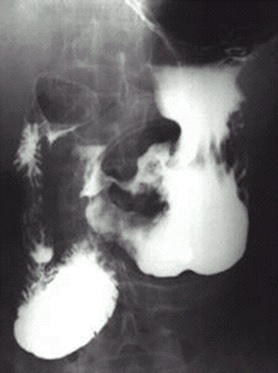

04卷-5.病史:男性,62岁,上腹不适,恶心、呕吐5个月,大便潜血阳性3周。诊断(本题满分2.00分)

胃癌

A.十二指肠球溃疡

B.胃溃疡

C.胃癌

D.胃炎

本题答案:C

题目解析:【该题针对“X线-消化道穿孔”知识点进行考核】